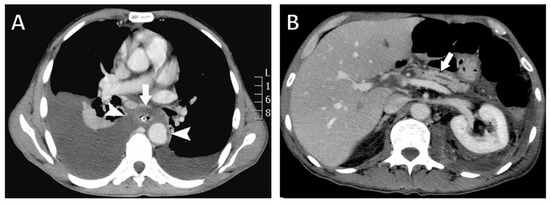

Bilateral Pancreaticopleural Fistula Masquerading as Thoracic Disease in Chronic Calculous Pancreatitis

Background: Pancreaticopleural fistula is a rare complication of chronic pancreatitis resulting from pancreatic duct disruption, typically presenting with pleural effusion and predominant respiratory symptoms. Bilateral pleural involvement is exceptionally uncommon and poses significant diagnostic and therapeutic challenges. Case Presentation: A 56-year-old [...] Read more.

Background: Pancreaticopleural fistula is a rare complication of chronic pancreatitis resulting from pancreatic duct disruption, typically presenting with pleural effusion and predominant respiratory symptoms. Bilateral pleural involvement is exceptionally uncommon and poses significant diagnostic and therapeutic challenges. Case Presentation: A 56-year-old man with a history of chronic alcohol abuse presented with progressive dyspnea and mild epigastric pain. Imaging revealed bilateral pleural effusions, an atrophic pancreas with a markedly dilated main pancreatic duct containing calculi, and a fistulous tract extending from the pancreatic body through the esophageal hiatus into the mediastinum. Magnetic resonance cholangiopancreatography confirmed the diagnosis of chronic calculous pancreatitis complicated by a pancreaticopleural fistula. After unsuccessful conservative management, the patient underwent distal pancreatectomy, resection of the fistulous tract, and Roux-en-Y pancreatojejunostomy. The postoperative course was uneventful, with complete resolution of pleural effusions and sustained clinical improvement. Conclusions: This case highlights the importance of considering pancreaticopleural fistula in patients with unexplained pleural effusions and minimal abdominal symptoms, particularly in the context of chronic pancreatitis. Bilateral involvement, although rare, should not preclude timely diagnosis. Appropriate diagnostic studies by computed tomography, magnetic resonance imaging, and magnetic resonance cholangiopancreatography are crucial for establishing the diagnosis. Surgical management offers definitive treatment in patients with ductal obstruction and calculous disease, resulting in excellent long- term outcomes. Full article